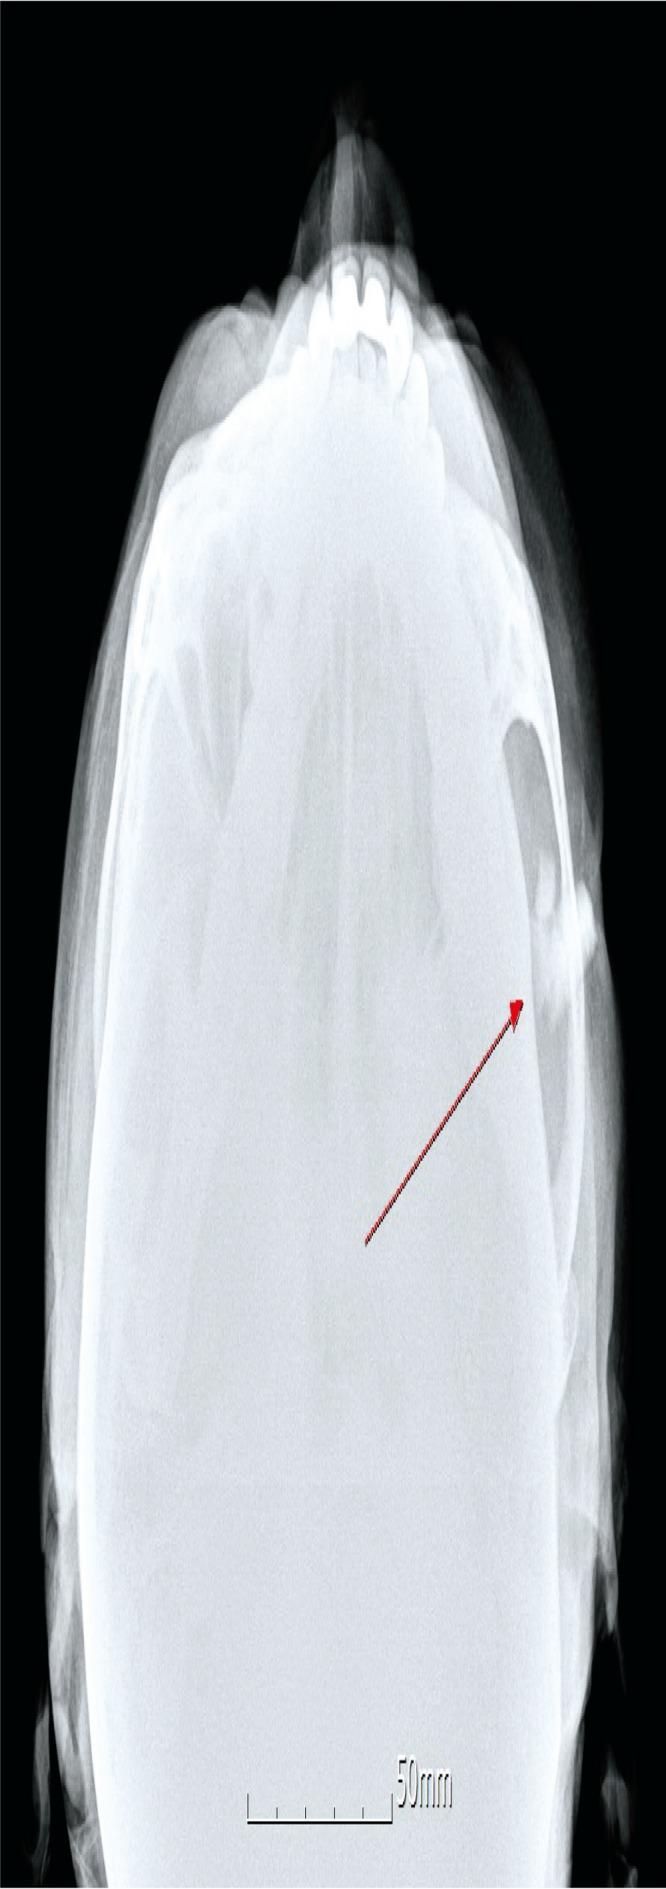

Foreign body (FB) impaction in the maxillofacial area could be caused by knives, glass fragments, and vegetative materials. We present the rare case of a 62-year-old man with a large glass FB in the left cheek retained for over 40 years. He had traffic accident over 40 years ago and glass fragments impacted on his left cheek. Glass fragments were retained around the zygomatic arch with dimpled scar and unclear serous discharge, but other facial motor or sensory dysfunction was not observed. We confirmed three glass fragments with radiologic examination including plain radiograph and computed tomographic image. Under general anesthesia, impacted glass fragments were removed through the direct incision on the dimpled scar and the additional incision on the left lateral canthal area. Remnant FBs were not seen on an intraoperative C-arm radiograph. After 2 days of irrigation for inflammation control, the dimpled wound was sutured. The wound was healed without major complication and the original dimpled scar was much improved.

摘要

异物(FB)嵌顿于颌面区域可由刀、玻璃碎片和植物性物质引起。我们报告一例罕见病例,一名62岁男性,左侧脸颊有一个大的玻璃异物,已留存40多年。40多年前他发生了交通事故,玻璃碎片嵌顿在他的左侧脸颊。玻璃碎片留存于颧弓周围,有酒窝状瘢痕且有不明浆液性分泌物,但未观察到其他面部运动或感觉功能障碍。我们通过包括X线平片和计算机断层扫描图像在内的放射学检查确认了三块玻璃碎片。在全身麻醉下,通过酒窝状瘢痕处的直接切口和左侧内眦区域的附加切口取出嵌顿的玻璃碎片。术中C形臂X线片未见残留异物。在进行2天的冲洗以控制炎症后,缝合酒窝状伤口。伤口愈合良好,无重大并发症,原来的酒窝状瘢痕明显改善。